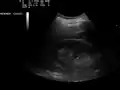

Ultrasound of liver (left side of the image) and right kidney (right side of the image) and Morison's pouch, not containing fluid -